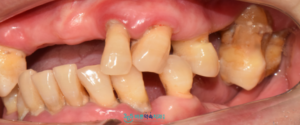

오늘 소개해 드릴 분은

다수의 치아를 상실하신 상태로,

치료를 위해 마포구청치과 365바른약속에

내원하신 환자분입니다.

환자분은 60대 여성으로,

치아를 상실한 지는 오래되었지만

치과에 대한 공포증과 당뇨, 고지혈증,

골다공증 등 전신 질환으로 인해

치료를 계속 미루셨다고 말씀해 주셨는데요.

먼저 구강 내 상태를

확인해 보았더니,

다수 치아가 상실된 채로

맞물리는 치아가 거의 없는

상황이었습니다.